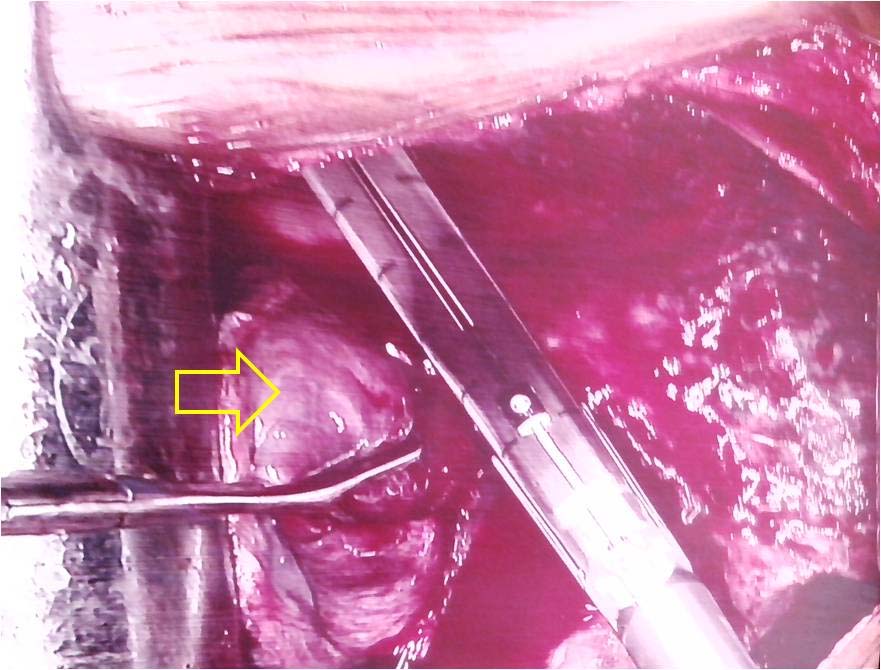

Left lower lobectomy was done. Intraoperatively large, fleshy, cystic, vascular mass involving whole left lower lobe with dense adhesion between lung mass and parietal pleura was observed [Table/Fig-3]. Resected specimen showed large cyst wall lined by necrotic debris along with multiple small cysts [Table/Fig-4]. Histopathological evaluation showed cysts lined by pseudostratified ciliated columnar epithelium with cystic and malformed bronchi and bronchioles. The findings confirmed the diagnosis of late onset left lower lobe Congenital Cystoadenomatoid Malformation (CCAM). On follow up satisfactory clinical and radiological improvement occur in nine month.

Intraoperative photograph showing large, fleshy, cystic, vascular mass involving left lower lobe.